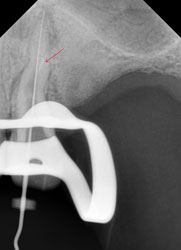

Но обычный рентгеновский снимок дает плоское 2хмерное изображение, разные структуры накладываются друг на друга, и сложную анатомию каналов на нем не всегда можно разглядеть. Что и произошло в этом случае. Один из каналов имел двойной изгиб. При предыдущем лечении доктор не смог по каким-то причинам этот изгиб увидеть и пройти, уперся в стенки корня, создав т.н. «ступеньку».

Это довольно неприятное осложнение, т.к. при повторном лечении «нащупать» снова реальный ход естественного канала очень непросто. А без этого невозможно рассчитывать на успех лечения. Представьте себе, что Вам надо наощупь, с закрытыми глазами вдеть нитку в самое маленькое игольное ушко… При этом ушко иголки находится в глубине канала диаметром всего 1-2 мм. Примерно с этим каждый раз сталкивается эндодонтист в таких случаях. В решении таких задач нужно большое мастерство, хорошее оснащение, пространственное мышление, изрядное терпение (причем и со стороны пациента тоже), ну, и доля удачи.